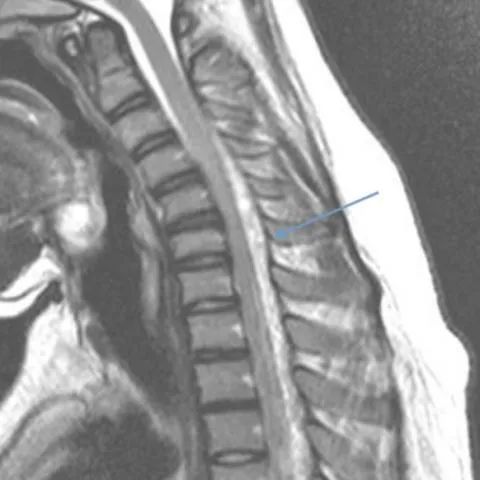

颈椎核磁共振在这种罕见疾病的诊断中起着重要的作用。矢状位磁共振成像显示细微的局灶性颈髓萎缩(图2 & 3),尤其是在下颈部。屈曲位成像示硬脑膜的前移位,后硬膜外腔增宽(图4)和更明显的脊髓变细,这在中立位不明显(图5)。

平山病是一种青少年型脊髓性肌萎缩症,其特征是手和前臂肌肉(C7-T1肌节)的单侧或不对称双侧受累。这种非进行性局灶性肌萎缩主要影响生命第二个十年的男性。感觉系统和肱桡肌的相对保留是这种肌萎缩的特征。虽然确切的机制尚不确定,但一些人认为脊柱和椎管内容物的不相称增长是短而紧的硬膜囊的原因,导致屈曲时脊髓受压。这一慢性过程导致脊髓前动脉区域的微循环障碍。中立位的MRI发现包括颈椎前凸丧失、局部脊髓变细或变平以及极少的髓内信号变化。屈曲位成像显示硬脑膜向前移位,导致后部硬膜外腔扩大。对比磁共振成像显示新月形强化硬膜外腔。颈椎在中立位和屈曲位的动态磁共振成像在诊断中是很重要的,尤其是在有典型临床表现的患者中。早期诊断是必不可少的,因为早期应用颈圈可以降低这种疾病的发病率。